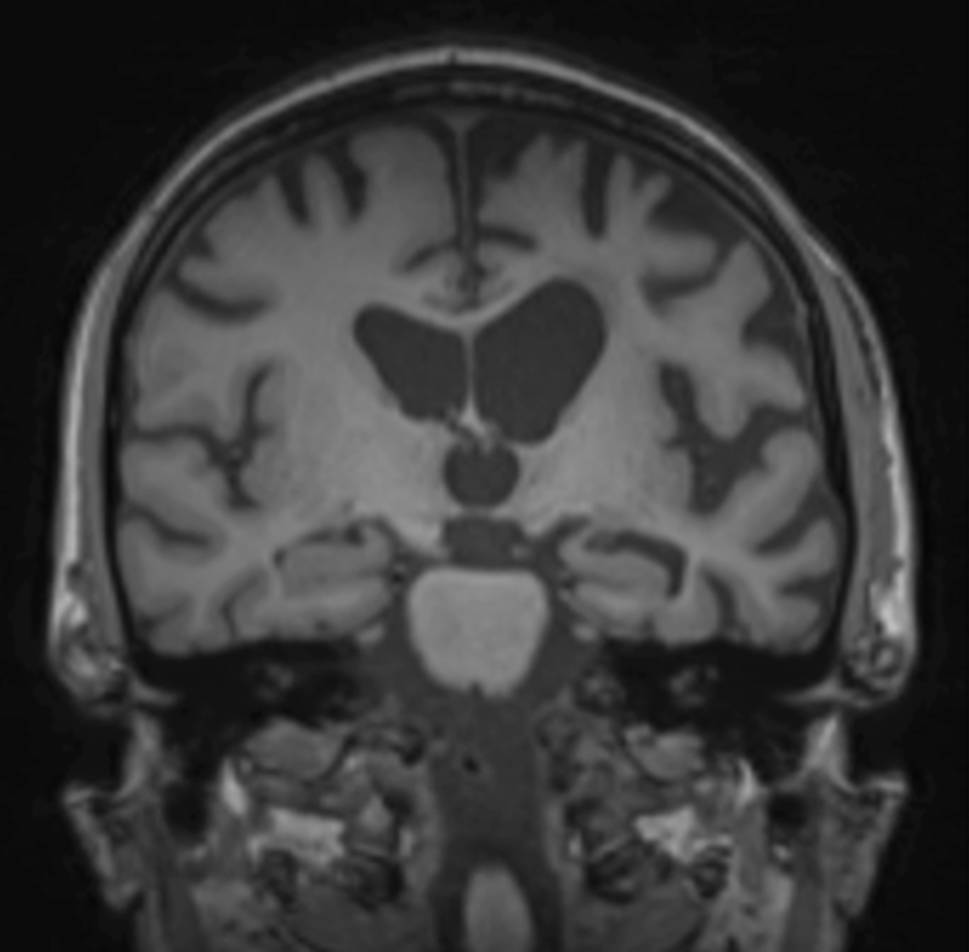

Global cortical atrophy

The four-step global cortical atrophy (GCA) scale proposed by Pasquier ranges from 0 = no atrophy to 3 = knife-blade atrophy (illustrated in Fig. 1; [1]). GCA 0 represents a normal volume of the gyri and a normal width of the sulci; GCA 1 indicates mild atrophy with a still-normal volume of the gyri but some open sulci; GCA 2 describes moderate brain atrophy with a reduction of gyri volume and a moderate enlargement of the sulci; and GCA 3 illustrates severe atrophy with severely reduced gyri and enlarged sulci. In addition, the focal regions of brain atrophy should be given.

Fig. 1

Global cortical atrophy scale